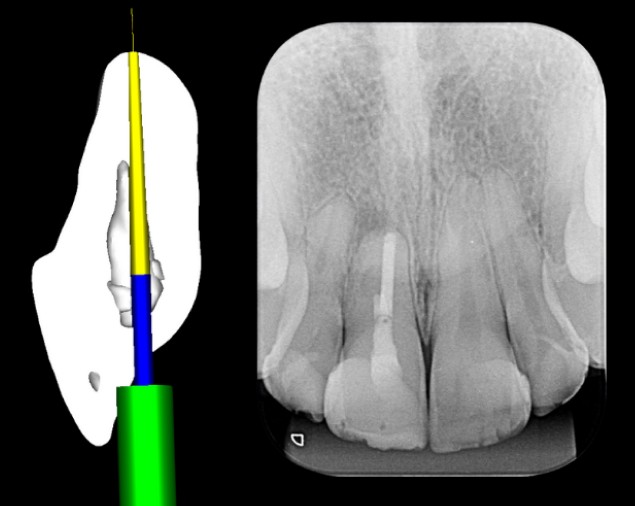

A Endodontia Guiada de Precisão emprega nova metodologia de planejamento com brocas e anilhas EG especialmente desenvolvidas para o segmento da Endodontia. O método permite ultrapassar calcificações radiculares e remover pinos de fibra de vidro de maneira previsível, rápida e conservadora, evitando desvio, e perda de elementos dentais.

Com a utilização da Endodontia Guiada de Precisão (Precision Guide), o acesso a canais calcificados e remoção de pinos de fibra de vidro é realizado de maneira segura, rápida e eficaz.

Princípios do Planejamento do Precision Guide

Planejamentos e Realização

Do exame ao guia impresso, veja como o planejamento digital torna o procedimento seguro, preciso e previsível, mesmo em casos complexos.